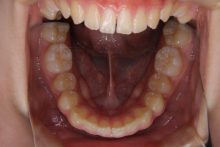

④叢生(そうせい)

叢生とは、歯が前後にデコボコと並んでいる状態や、ガタガタになっている歯並びのことをいいます。

乱杭歯(乱ぐい歯)とも言われます。歯列がデコボコになっているので、歯磨きをしても歯ブラシの先がちゃんと届かずに、虫歯や歯周病になりやすくなります。

八重歯もこの1つで叢生になります。